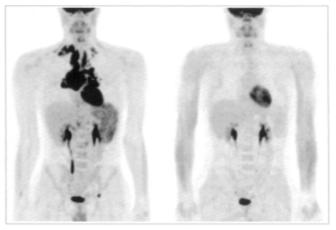

МРТ изображения органов грудной полости представлены на рисунках 13-15. МРТ Исследование грудной полости проводят с ЭКГ-синхронизацией, чтобы избежать артефактов от движения сердца и пульсации сосудов. Обычно используют импульсную последовательность спин-эхо для получения Т1взвешенных изображений. Просветы сосудов и полости сердца при этом выглядят темными за счет потери МР - сигнала от движущейся крови (времяпролетный эффект). Степень потери сигнала напрямую связана со скоростью движения.

а

б

Рис. 13. Т1-ВИ органов средостения в аксиальной проекции на уровне верхнего этажа: а – уровень пяти сосудов; б – уровень дуги аорты.

1 – правый плечеголовной венозный ствол,

2 – левый плечеголовной венозный ствол,

3 – правый плечеголовной артериальный ствол,

4 – левая общая сонная артерия,

5 – левая подключичная артерия,

6 – трахея,

7 – пищевод,

8 – дуга аорты